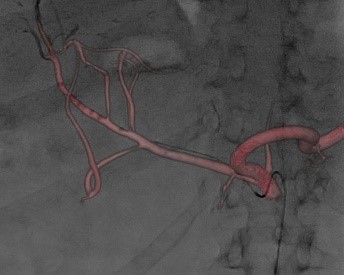

Програмне забезпечення 3D реконструкції

В основу покладена робота в режимі 3D DA або 3D DSA. Зйомку можна виконувати як з операційної, так і з пультової кімнати для зменшення дози на персонал, зі швидкістю обертання С-арки до 50°/с.

Численні режими візуалізації та реконструкції: